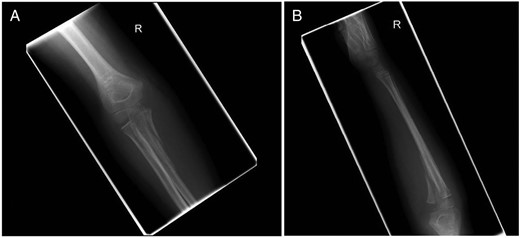

Under general anaesthesia, the fracture was clearly visualized using a medial approach to the proximal ulna, splitting the flexor muscle mass longitudinally. Minimal dissection was required distally secondary to a traumatic defect in flexor carpi ulnaris. The ulnar nerve was identified and protected throughout. Following reduction the fracture was fixed securely using 2 × 4.0 mm partially threaded cannulated screws; the guide wires were passed in an anterior to posterior direction and the screws were inserted from posterior to anterior through two separate stab incisions on the subcutaneous ulnar border for ease of removal in the future. The elbow was taken through a full range of motion and satisfactory fluoroscopic images were obtained (Fig. 3). A posterior long arm back slab was applied and completed the following day prior to discharge.

(A) Anterior–posterior and (B) lateral fluoroscopy images with two cannulated screws in situ. Fluoroscopy images taken in theatre post-fracture fixation.